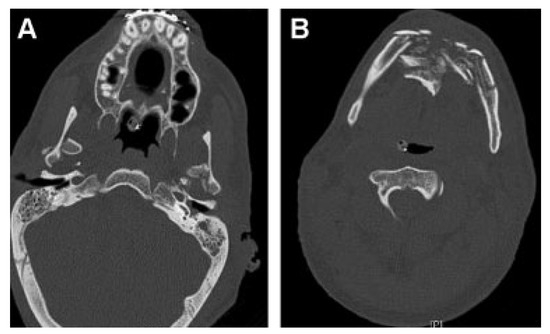

Figure 12.

(A,B) Computed tomography scans show comminuted anterior mandibular and bilateral condylar fractures. Fractures were stabilized with MMF for 12 weeks. (Images are courtesy of Colonel Robert Hale.) MMF, maxillomandibular fixation.

Patient 4 arrived in critical condition at BAMC 3 days after injury. He remained in serious condition for 5 months with his burn injuries constantly threatening his life. During this period and immediately afterward he underwent multiple burn, orthopedic, and general surgery procedures. Because of the severity and extent of his facial burn injuries, which limited conventional surgical approaches, reconstruction of his facial fractures was delayed. The patient remained in MMF for 12 weeks.